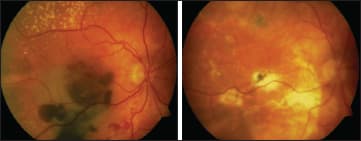

The next strategy Dr. Szurman discussed was full macular translocation (FMT). In Dr. Szurman's own practice's experience with this procedure, patients with hemorrhages experienced stabilization with mild visual improvement. In certain cases, he noted, the improvements in visual acuity were quite impressive (Figures 1 and 2). Further improvements were limited by the complication rate.

Figure 1. This patient's vision was counting fingers (left), but after FMT, logMAR VA of 0.125 was recovered (right).

Figure 2. This patient's vision was logmar 1/35 (left), but after FMT, logMAR VA of 0.32 was recovered (right).